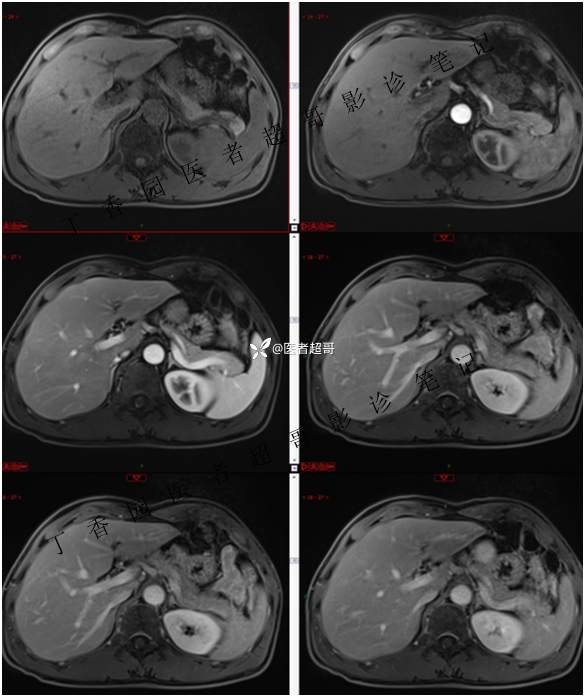

肝胃间隙肿瘤,间质瘤?平滑肌瘤?还是鞘瘤?有结果,请分析!

主 诉:查体发现肝占位3天。

现病史:患者于3天前查体行肝胆脾胰肾彩超示肝内实性占位,无恶心、呕吐,无发热、寒战,无腹胀、腹泻,进一步于医院行上腹部CT增强示:肝胃交界处肿块。未行特殊治疗。今患者为求进一步治疗,来我院就诊,门诊以“肝占位性病变”收入院。患者自发病以来,神志清,精神可,饮食睡眠可,二便可,体重近期未见明显变化。